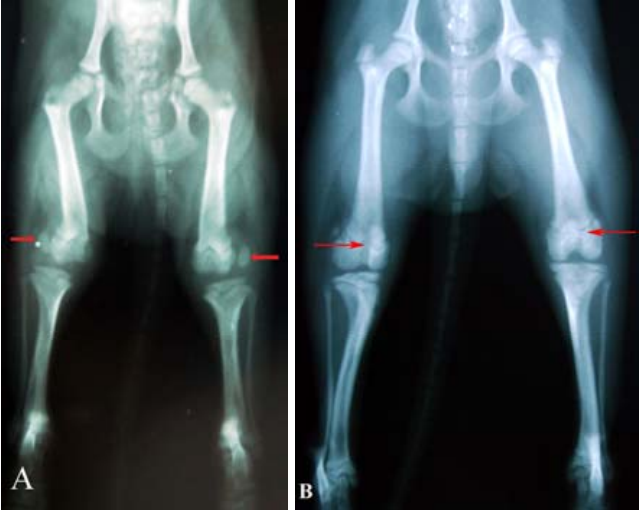

膝蓋骨異位X光

就診對象:一隻 7 個月大的博美犬(公犬),小型犬,後肢左右兩側皆有膝蓋骨異位問題。

就診原因:飼主發現狗狗走路時後腳不太穩定,活動時偶爾出現跛行的情形,跑步與跳躍明顯減少。雖然平時仍能行走,但站立時後腳姿勢看起來不自然,長時間活動後症狀會更加明顯,因此帶來就診評估。

臨床檢查:獸醫師在理學檢查中發現,狗狗的兩側膝蓋骨都容易向外側滑出正常位置,屬於外側膝蓋骨異位(LPL)

• 膝蓋骨在大多數時間處於脫位狀態,但仍可手動推回原位

• 膝關節穩定度不足,後肢排列略有偏移

• 伴隨輕度大腿肌肉萎縮

X 光檢查顯示:

• 膝蓋骨未穩定落在股骨滑車凹槽內

• 滑車凹槽偏淺,無法有效固定膝蓋骨位置

綜合臨床與影像檢查後,確診為雙側中度外側膝蓋骨異位(第 III 級)